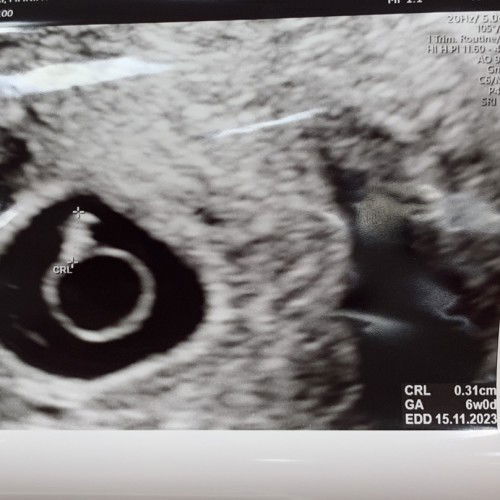

สวัสดีค่ะ คุณแม่ ICIS ตั้งวันกำหนดคลอดจากวันย้ายตัวอ่อนหรือนับครรภ์แบบปกติจากประจำเดือน รบกวนขอความคิดเห็นเพราะดิฉันหากนับครรภ์ปกติ คือ 8 สัปดาห์ แต่เมื่อไปตรวจ ultrasound baby ขนาดเท่ากับ 6 weeks (ตรงตามแบบนับวันจากการย้ายตัวอ่อน) ใครเป็นแบบนี้ บ้างคะ แล้ว ใช้นับครรภ์แบบไหน ตาม ขนาด ultrasound หรือไม่คะ ขอบคุณค่ะ #icis #ivfcommunity #ivf ขอคำแนะนำค่ะ